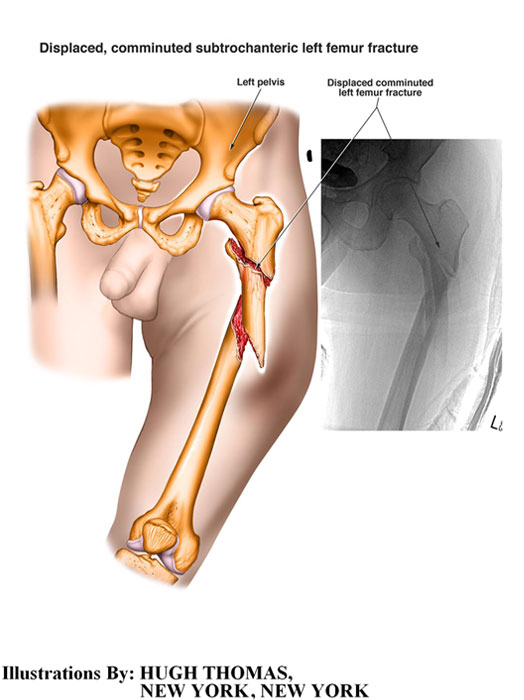

The medical illustrations on this page are examples of the details the attorneys at the Law Offices of William Cafaro prepare for jury presentations.